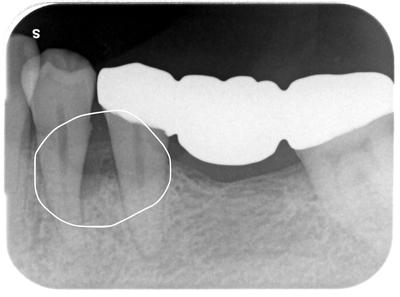

術後

多田_直樹_ライトボックス(1)_口腔内_20210826_100319 2.jpg

術前◯内の骨が再生しているのが分かる。

安定している。

今回は通常の歯周病外科処置のみであり、BGR、骨移植、骨誘導因子の使用等は行っておらず、単純に歯肉を開いて歯根面をデブライメント行っただけです。